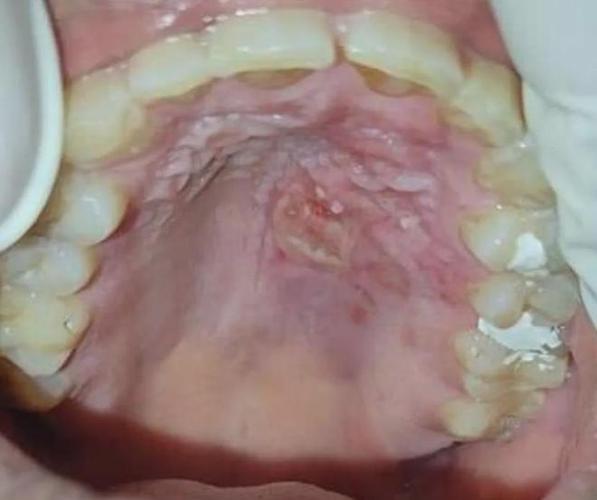

听到您说口腔溃疡变成了一个“洞”,这听起来确实很令人担忧,正常的口腔溃疡(阿弗他溃疡)通常是浅表的圆形或椭圆形溃疡,表面有黄色假膜,周围有红晕,一般不会形成“洞”。

口腔黏膜的损伤或病变如果比较深,累及到黏膜下层甚至更深层的组织,愈合时就可能形成凹陷或“洞”,这比普通溃疡要严重一些,可能的原因包括:

癌性溃疡

- 原因:这是最需要警惕的情况,口腔癌(如鳞状细胞癌)的早期可能就表现为一个长期不愈合的、质地硬的、边缘隆起、中央凹陷坏死(类似火山口)的溃疡。

- 特点:

- 长期不愈:超过2周甚至一个月以上仍不愈合,或愈合后又反复在同一部位复发。

- 形态异常:溃疡边缘不整齐,呈菜花状或火山口样,基底硬,摸起来像小石子一样。

- 疼痛性质改变:早期可能不明显,但后期疼痛剧烈,并向耳部、颞部放射。

- 伴有其他症状:可能伴有口腔麻木、张口困难、颈部淋巴结肿大、不明原因的体重下降等。